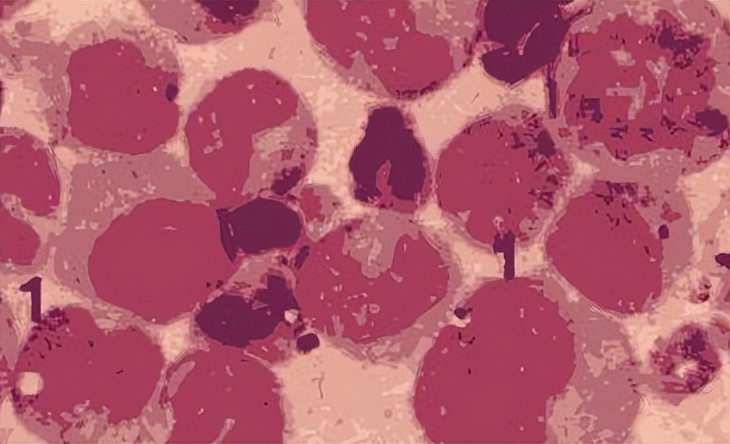

败血病是一种由细菌引起的严重感染病,通常在血液中引起一系列的炎症反应。败血病通常在身体内的某个部位引起感染,如肺部、泌尿生殖系统、肠道等,随后病原体可以通过血液循环进入全身器官和组织,导致多器官功能障碍综合症。败血病常见的症状包括高热、寒战、头痛、恶心、呕吐、皮肤瘙痒和全身不适等。

然而,这个故事显然是虚构的,败血病的病原体是由微生物引起的,而不是由人体内的血液混合物引起的。实际上,败血病是在19世纪初期被正式描述和命名的。当时,医生们注意到一些病人在接受手术或分娩等医疗操作后出现了高热、寒战、心跳过速等症状,随后很快就死亡了。这些病例引起了医生们的关注和研究,他们发现这些病人的血液中存在一种致病微生物,后来被命名为葡萄球菌。

另外,一些其他的医生也开始对败血病的病原体进行研究。他们发现,在败血病病人的血液中存在一种致病微生物,后来被命名为葡萄球菌。这项发现极大地促进了对败血病的认识和治疗。